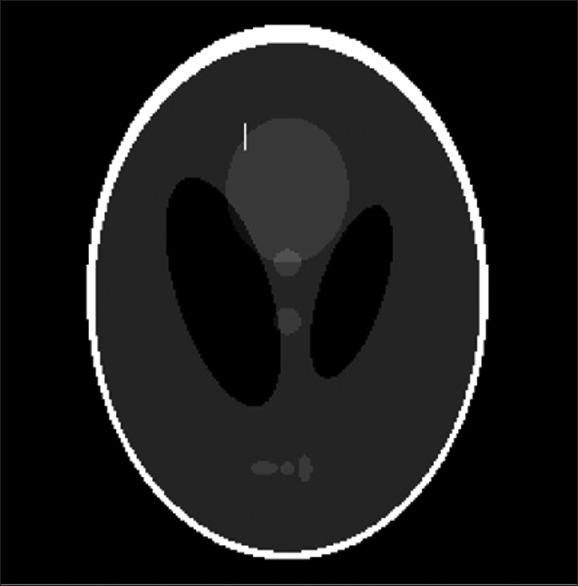

The contributing detectors for a given pixel and a given projection view, and the length of corresponding intersection lines with pixels, are calculated using our proposed algorithm. For the hybrid method, the respective narrow-angle fan beam was modeled by multiple equally spaced lines. The computed system matrix was evaluated in the context of reconstruction using the simultaneous algebraic reconstruction technique (SART) as well as maximum likelihood expectation maximization (MLEM).

The proposed LIM offers a considerable reduction in calculation times compared to the standard Siddon algorithm: 2.9 times faster. Differences in root mean square error and peak signal-to-noise ratio were not significant between the proposed LIM and the Siddon algorithm for both SART and MLEM reconstruction methods ( > 0.05). Meanwhile, the proposed hybrid method resulted in significantly improved image qualities relative to LIM and the Siddon algorithm ( < 0.05), though computations were 4.9 times more intensive than the proposed LIM.